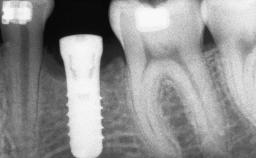

Guided Bone Regeneration (GBR) with a Particulated Autologous Graft and a ePTFE-Reinforced Membrane for Vertical Augmentation of a Single-Tooth Edentulous Space in the Esthetic Zone

# of Implants 1

Type of Implants Two-Piece

Bone Augmentation Staged|Vertical

Placement Protocol Early or late implant placement